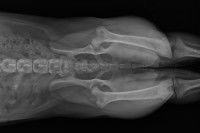

Pour tout ce qui concerne les troubles locomoteurs, l’imagerie vient souvent à mon secours si elle n’a pas déjà été réalisée : une radio, un scanner ou un IRM affinent le diagnostic, et permettent parfois de comprendre pourquoi les objectifs de la séance n’ont pas été atteints – ils ne pouvaient tout simplement pas l’être, puisque je n’étais pas la bonne personne à qui s’adresser. J’invite d’ailleurs parfois le propriétaire à faire réaliser d’abord certains examens complémentaires (avec l’accord de son vétérinaire) pour être sûre que la solution n’est pas avant tout d’ordre chirurgical.

Par exemple, dans le cas d’une rupture du ligament croisé du genou d'un chien, la solution est fondamentalement chirurgicale. L’ostéopathie peut être utile, mais uniquement pour aider l’animal à retrouver une bonne mobilité une fois qu’il a été opéré.

C’est la même chose pour les problèmes de fracture : parfois, elles ne sont pas évidentes à repérer (c’est le cas notamment pour celles aux phalanges), si bien que le propriétaire vient me voir alors qu’en fait je ne suis pas le bon interlocuteur.